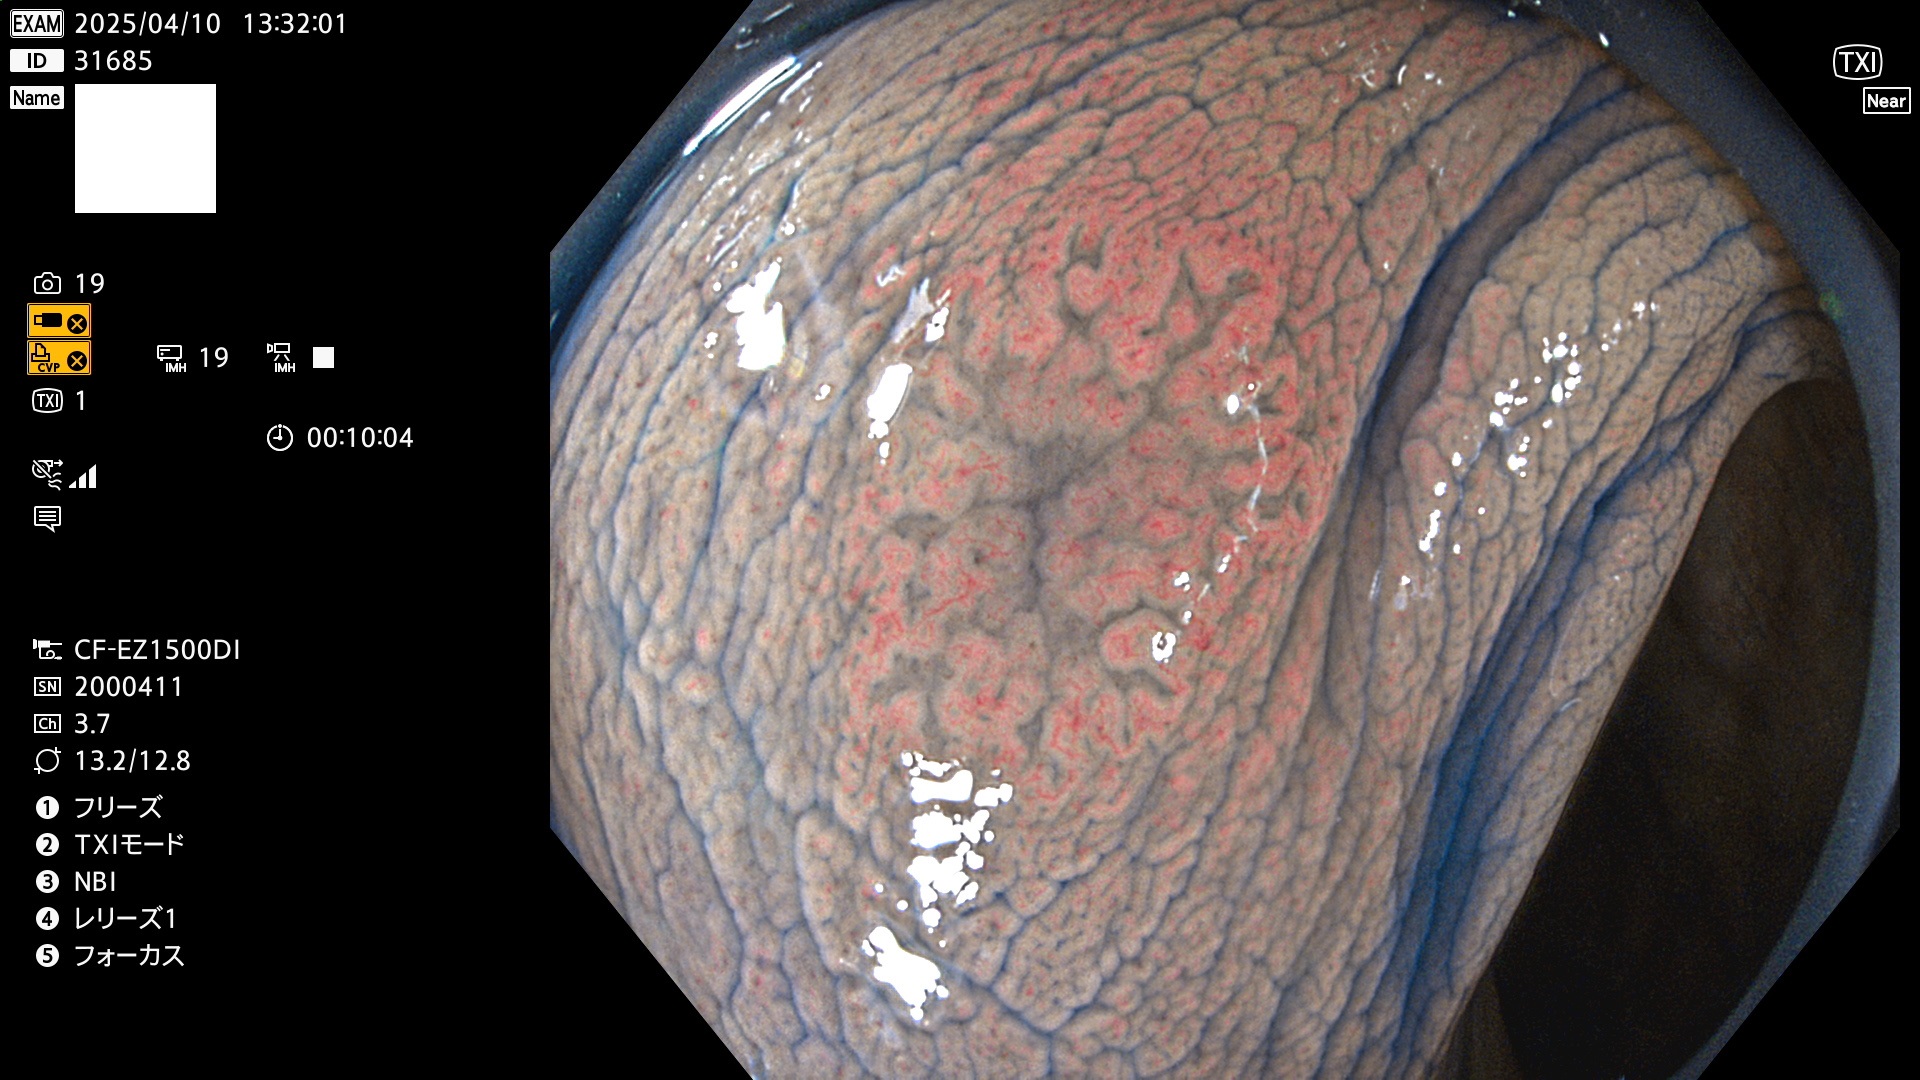

抽出の対象期間 2025年4月10日〜4月13日の4日間(48件の検査)11個 (4/48=23%)

びらんと鑑別の困難なUc型腺腫